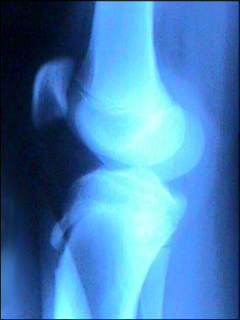

Bone Muscle Joint

Osgood-Schlatter disease